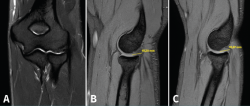

La resonancia magnética (RM) permite identificar cambios que incluyen el aumento de la señal del tendón dentro o alrededor de la inserción, engrosamiento del tendón o una discreta colección de líquido entre la cápsula lateral y el tendón extensor (Figura 8). La mayoría de los pacientes con síntomas de tendinopatía lateral crónica muestran cambios de señal en la RM y se ha podido relacionar la proporcionalidad entre la severidad de los cambios y la sintomatología del paciente(17). Ofrece ciertas ventajas frente al resto, como el hecho de que es más reproducible, reduce la variabilidad interobservador y ofrece más información acerca de la patología intraarticular(18). En ciertos entornos, sin problemas para obtener RM de calidad en periodos cortos de tiempo, se utiliza la RM para cuantificar el espesor de la lesión y la localización superficial o profunda de la misma y en función de dichos hallazgos planificar un abordaje abierto o artroscópico. En medios con dificultades para obtener RM en todas las sospechas de tendinopatía lateral de codo(19), la ecografía puede ser útil para diagnosticar de manera adecuada esta patología en la mayoría de los pacientes, lo que permite reservar la RM para pacientes con síntomas cuyos hallazgos ecográficos sean normales.(20).

Figura 8. Cambios vistos en resonancia magnética en paciente con dolor en la cara lateral del codo. Aumento de la señal del tendón dentro (flecha) o alrededor de la inserción, engrosamiento del tendón y una discreta colección de líquido entre el ligamento colateral lateral.